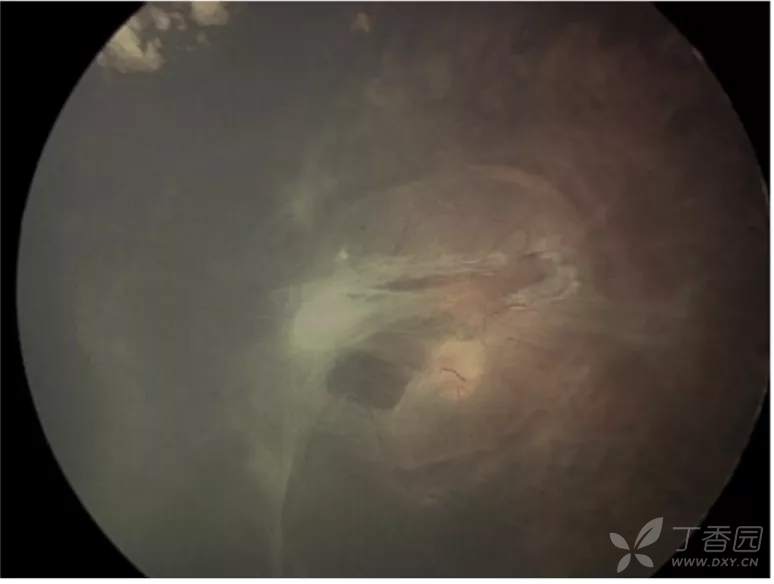

07、急性早产儿视网膜病变5期:完全视网膜脱离

图. 5A期:视网膜完全脱离并可见视盘,提示开放漏斗型脱离。

图. 5B期:由于纤维血管组织,视盘不可见。

图. 5B期:外部照片眼前节正常,由于晶状体后纤维血管组织形成,视盘或视网膜不可见。B超显示完全性视网膜脱离,呈后部闭合漏斗状结构。

图. 5C期:眼前段特征改变为晶状体前移位、明显的前房变浅、中央虹膜-晶状体前囊膜-角膜内皮粘连,中央区角膜混浊(星号),无法观察到闭合漏斗状视网膜脱离。